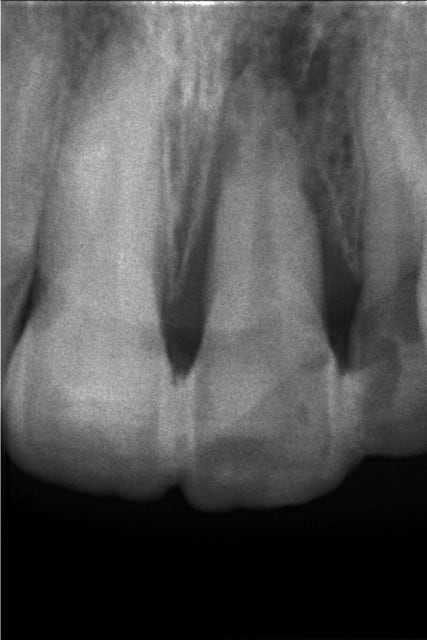

Hier j'ai donc ouvert la dent et nettoyé irrigué. La radio est de mauvaise qualité mais on voit qd même une bonne lésion apicale et une cratérisation de l'os alvéolaire ainsi que , il me semble, des résorptions internes et externes.

voila la radio

Euh, c'est pas une lésion apicale, c'est une résorption ext.

Ta dent est morte (comme le perroquet), la cratérisation est importante aussi..